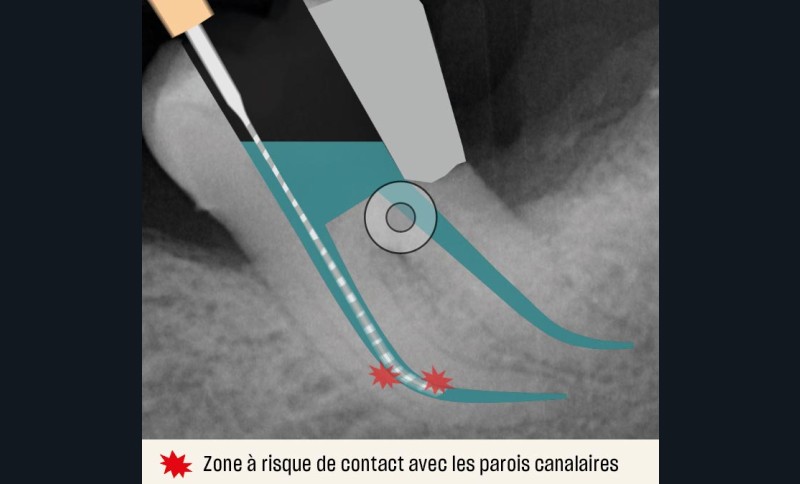

Une conicité trop importante

Si elle optimise le pronostic endodontique, une conicité trop importante (fig. 9) pourrait compromettre le pronostic biomécanique par un travail trop important de la dentine péricervicale, pouvant entraîner un stripping, voire une perforation dans certaines zones à risque (par exemple la paroi disto-linguale de la racine mésio-vestibulaire (MV) d’une première molaire mandibulaire).

Optimisation de la désinfection

Les limites lors de la désinfection résident dans les contraintes inhérentes à la diffusion des solutions dans un espace canalaire confiné, voire étroit, ayant une conicité réduite (entre 4 % et 6 %) [22, 23]. De plus, l’utilisation de systèmes « mono-instrumentaux » augmente considérablement la production de boue dentinaire créée au passage de chaque lime mécanisée. La principale limite en termes de désinfection est la mauvaise diffusion des fluides dans un espace étroit. Dans les préparations canalaires à conicité réduite, les solutions d’irrigation circulent mal et l’optimisation de la désinfection devient alors indispensable. Pour augmenter le temps de contact des solutions d’irrigation avec l’ensemble du réseau endocanalaire, le recours à des moyens d’activation existe. Les principaux (manuel, seringue, sonore et ultrasonore) [tableau 1] présentent des avantages et des inconvénients (fig. 11), mais aucun n’a montré de supériorité par rapport à une autre technique quant à leur effet antibactérien [24].